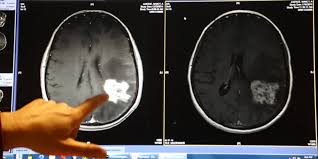

Az áttörésnek minősített gyógymódok listájára vette fel az amerikai gyógyszerfelügyelet az észak-karolinai Duke Egyetem kísérleti módszerét az agydaganat egyik formájának, az agresszív glioblasztómának a kezelésére.

A CBS televízió vasárnap este riportban mutatta be a módszert, amelynek lényege, hogy a gyermekbénulás vírusát közvetlenül a koponyában terjeszkedő daganatba juttatják.

A jelenleg is kezelés alatt álló 58 éves Nancy Justice-nál 2014 októberében állapítottak meg gliobasztómát, s az orvosok közölték vele: hét hónapja van hátra. A tévé beszámolója szerint az asszonyt most kezelik a gyermekbénulás vírusával, az eljárás eddig sikeres, a daganat csaknem teljesen eltűnt.

Stephanie Lipscombnál 2011-ben, húszesztendős korában diagnosztizálták az agydaganatot, megműtötték, majd a betegség 2012-ben kiújult. Ekkor vágott bele a Duke Egyetemen alkalmazott kezelésbe, a minap Joe Biden alelnök is találkozott vele.